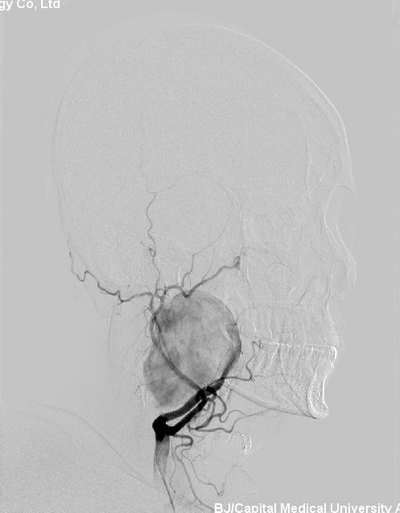

2013年3月27日,北京安贞医院脑卒中中心主任、中美脑中风协作组中方组长张勤奕教授于安贞医院为一例颈内动脉巨大血管瘤患者施行了手术,手术圆满成功。

患者入院后完善DSA检查提示“右颈内动脉C1段巨大血管瘤”患者动脉瘤有破裂出血风险,可危及生命,手术风险大。2013年3月27日,张勤奕教授于安贞医院为其施行了手术。手术于杂交手术室进行,术中造影检查动脉瘤远端血流情况后,将患者颈内动脉缝扎,降低动脉瘤压力。手术圆满成功,患者恢复良好。